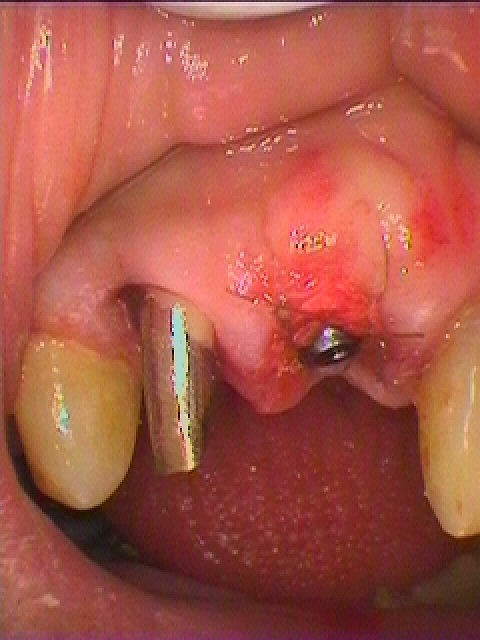

ブログ一覧|広島市安佐南区の歯科医院 ブログ一覧 トップ ブログ一覧 お知らせ スタッフブログ ブログ一覧 お知らせ 2019/04/17 一般治療の現状 破折歯の対応 天然歯牙の弱さ お知らせ 2019/04/17 歯を抜くようになり、インプラントを埋入する医院を探していた 左下7番最後臼歯のインプラント埋入 お知らせ 2019/04/16 フルマウスのリコンストラクション 咬合再構成 お知らせ 2019/04/16 埋入後のインプラント CTによる埋入後のイメージとのすり合わせ お知らせ 2019/04/16 抜歯即時インプラント埋入 右上1番埋入時 お知らせ 2019/04/16 外傷により前歯部の歯が折れている インプラントを考えたいとのこと お知らせ 2019/04/15 インプラントの上部構造もチタンのアバットメントとセラミックにて作成していきます お知らせ 2019/04/15 前歯部4本ジルコニアクラウン4連冠の作成 << 1 2 3 4 5 … 416 417 418 419 420 … 870 871 872 873 874 >> Web診療予約 初めての方へ 選ばれ続ける理由 院内設備について 歯が痛いしみる一般歯科 歯がぐらぐらする歯周病 健康な歯を保ちたい予防歯科 子供の虫歯予防をしたい小児歯科 銀歯をセラミックに審美歯科 白い歯を目指しませんか?ホワイトニング 矯正専門医がいるので安心矯正歯科 抜けた歯を補いたいインプラント・入れ歯 医院案内 スタッフ紹介 メリィハウス歯科クリニックオフィシャルホームページ ラベンダー歯科クリニックオフィシャルホームページ お知らせ・ブログ ホーム 診療科目 一般歯科 歯周病治療 予防治療 小児歯科 審美治療 ホワイトニング 矯正歯科 入れ歯・インプラント マウスピース矯正 初めての方へ 院長・スタッフ 設備紹介 医院案内・アクセス メニューを閉じる